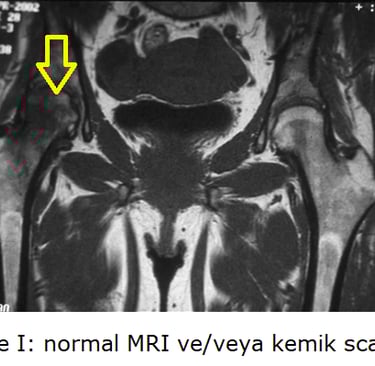

Evre 0: Röntgen ve MR normal. Semptom yok / Şüphe. (LR+ = 1.0)

Evre I: Röntgen normal, MR pozitif (Çift Çizgi). Hafif ağrı. (LR+ 15.0 - Tanı kesin)